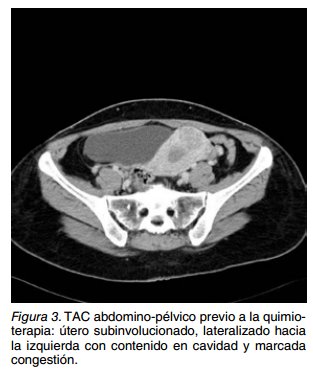

Estabilizada la paciente se solicitó un TAC tó- raco-abdómino-pélvico con contraste, que mostró hepatoesplenomegalia homogénea, uréter izquierdo dilatado sin repercusión por compresión del mismo por útero subinvolucionado, lateralizado hacia la izquierda con contenido en cavidad y marcada congestión (Figura 3). Pequeños ganglios retroperitoneales de <7 mm y un ganglio inguinal de 12 mm. Se realizó TAC y RM cerebral sin hallazgos signifiativos.